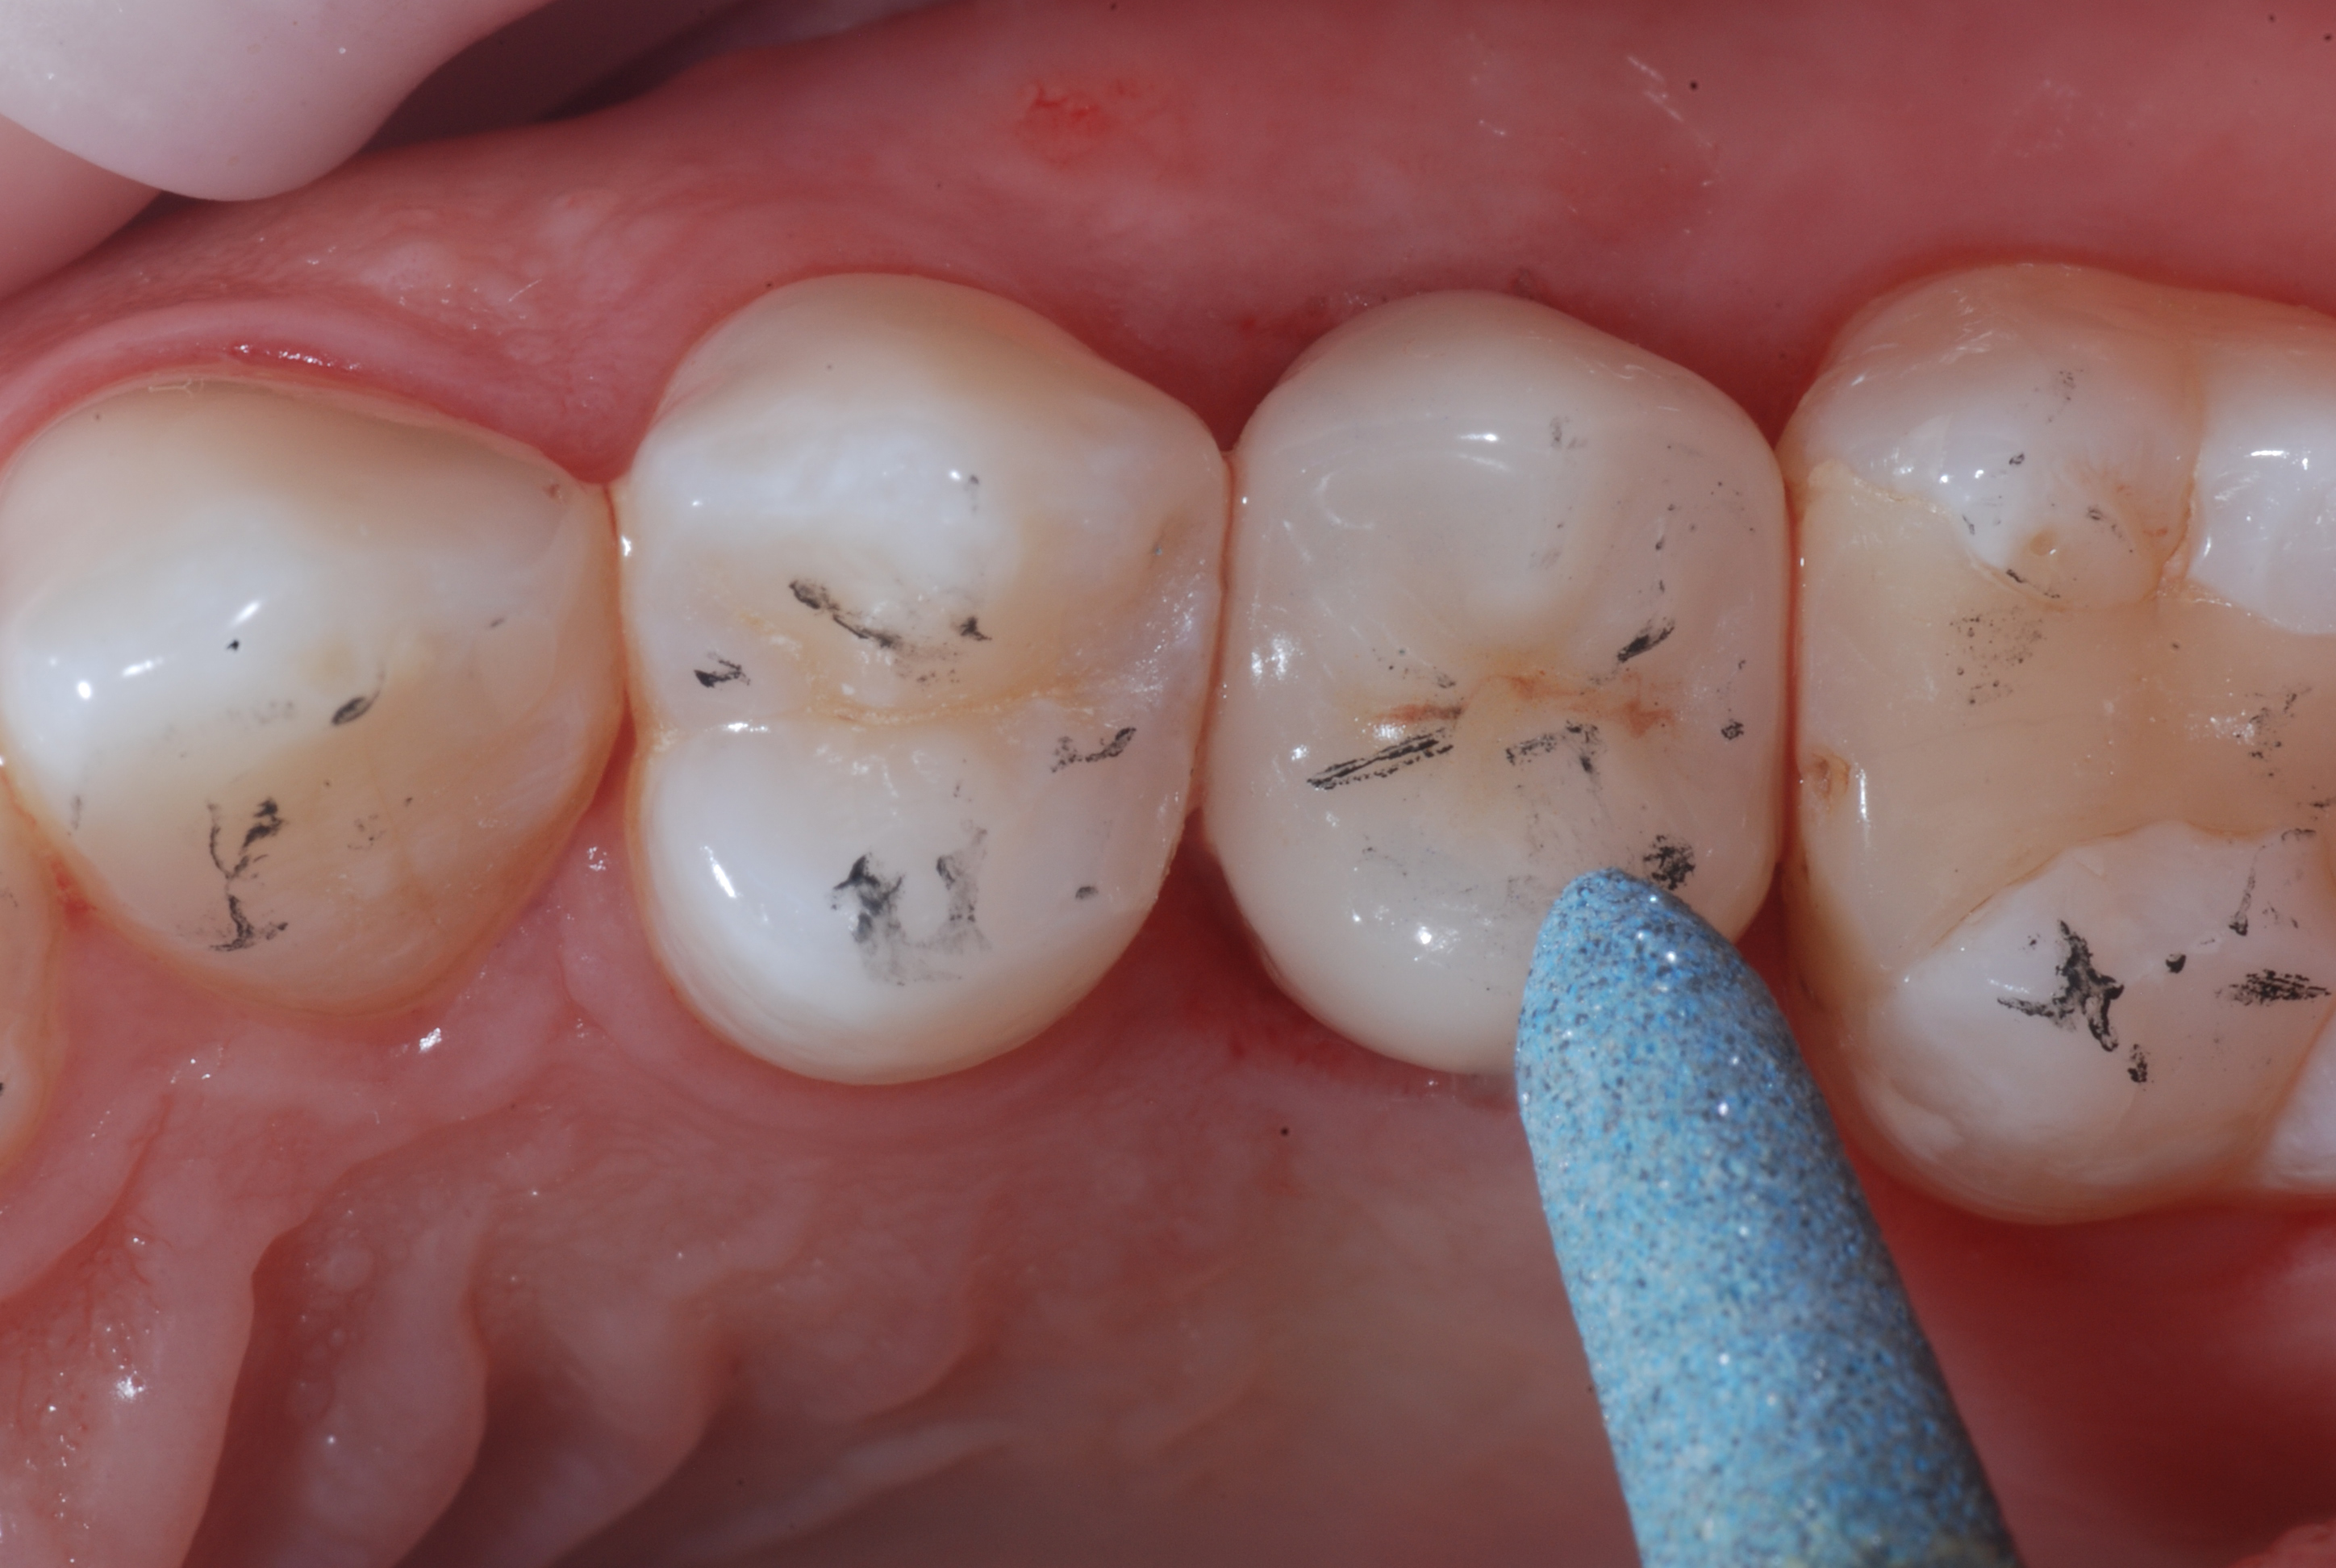

Figure 7

Figure 8

Figure 7. Milled lithium disilicate crown (Mr. Paolo Vigiani).Figure 8. The pass of the eZr Garrison coarse-grained blue rubber point immediately after cementation of the crown with a self-adhesive cement and occlusal adjustments made with a fine-grained diamond bur.

After the occlusal adjustment was performed with fine-grained diamond burs, the final polishing is carried out with eZr Garrison rubber polishers. The first step was performed with the coarse-grained blue rubber point to eliminate the microgrooves created by the diamond bur. Subsequently, the green medium-grained point was applied, which prepares the surface for the final polishing by the orange fine-grained point. Through these simple three steps, a perfectly smooth surface was obtained which is comparable to a glaze.  Unlike an unpolished surface which is rather abrasive for the opposing teeth, the mechanical polishing obtained with the eZr rubber polishers produces a shiny and an absolutely brilliant surface which is nonabrasive for the opposing teeth.

Figure 9. The pass of the eZr Garrison medium-grain green rubber point.Figure 10. The pass of the eZr Garrison finegrained orange rubber point.